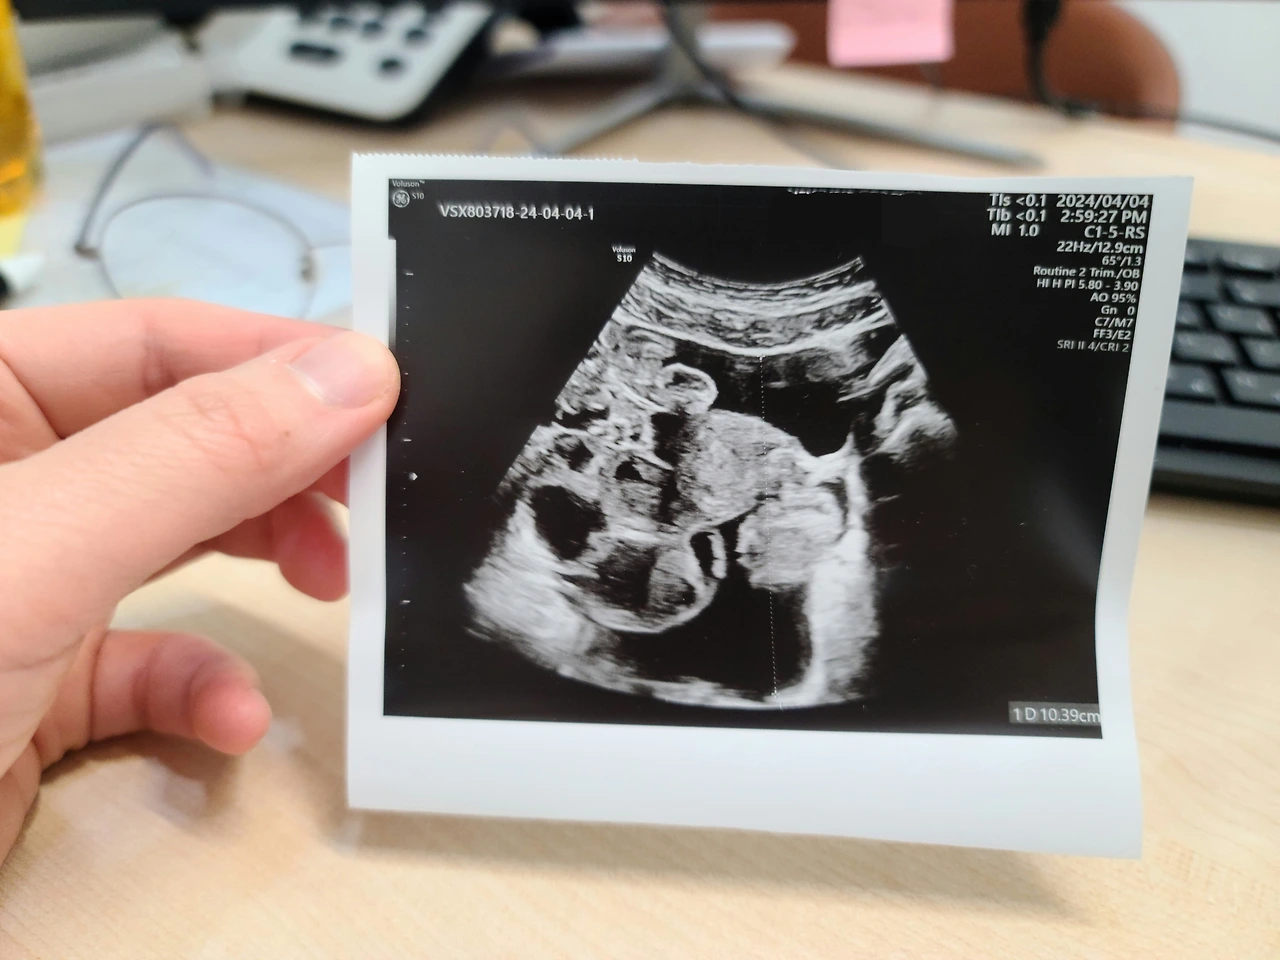

그리고 어제부터, 즉 배아 이식을 한 지 이틀 차부터, 꽤 악력 좋은 누군가의 주먹이 내 뱃속을 잡고 있는 느낌이 들었다. 그래서 배 초음파를 대어보았더니, 골반 높이까지 복수가 차 있었다. 심한 경우 배 전체가 복수로 미어지기도 하니, 이 정도면 양반이다. 어쨌든 지하철을 못 타거나, 진료나 수술을 못 할 정도는 아닌데 여하튼 몸이 가뿐하지 않고 어딘가 불편한 상태이다.

막간을 이용한 셀프 초음파. 까만 건 물이고, 하얀 건 장기이니라